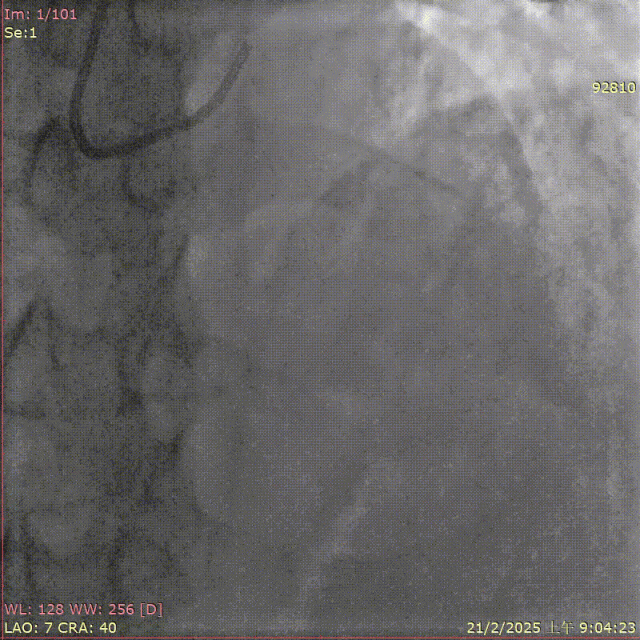

术前造影

术后造影